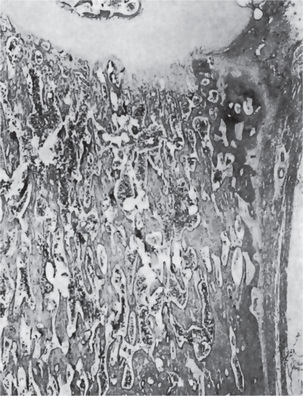

The bones in patients with osteogenesis imperfecta exhibit thin cortices, sometimes being composed of immature spongy bone, while the trabeculae of the cancellous bone are delicate and often show microfractures (Fig. 17-1). Osteoblastic activity appears retarded and imperfect, and for this reason the thickness of the long bones is deficient. The basic defect appears to lie in the organic matrix with failure of fetal collagen to be transformed into mature collagen. Qualitative defects (abnormal collagen I molecule) and quantitative defects (decrease in production of normal collagen I molecules) both exist. There is some evidence that the progressive intermolecular cross-linkage of adjacent collagen molecules, which is an essential characteristic of normal collagen maturation, is defective in this disease. Calcification proceeds normally. Defective microvascular system and decreased collagen fibril diameter have also been observed. The length of the long bones is usually normal unless multiple fractures have caused undue shortening.

Figure 17-1 Osteogenesis imperfecta (OI).

The typical microscopic changes of OI can be seen in a section of a long bone of a severely affected child. The bone cortex is thin and porous. The bone trabeculae are thin, delicate, and widely separated. Many osteoblasts and osteocytes are present, but the formation and organization of osteoid is deficient. There is less bone tissue than normal and most of it is woven or nonlamellar bone with collagen fibers of small size and random distribution. The woven bone has an increase in basophilic ground substance (shown by blue staining in H and E sections). (Courtesy of Dr Robert C Mellors)